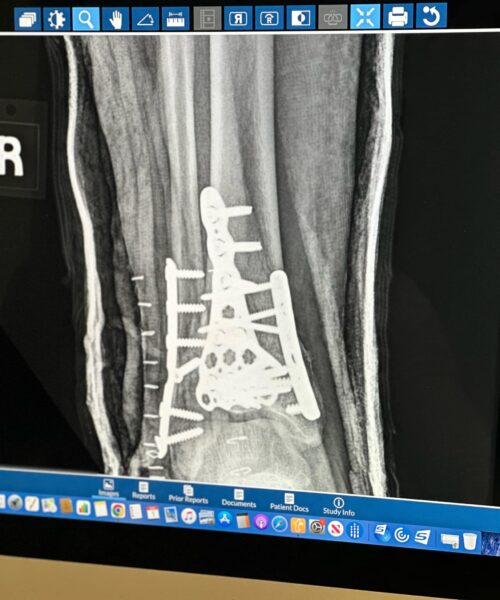

First Xray Post Surgery - February 2024